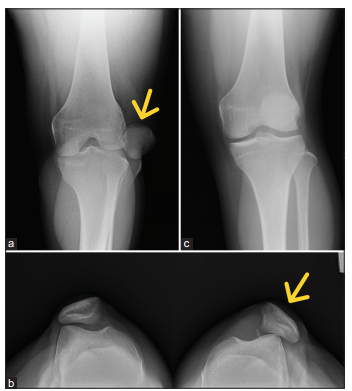

Bệnh nhân nữ, 20 tuổi, không có bệnh lý nền, bị chấn thương trong lúc nhảy – tiếp đất khi đang khiêu vũ, gây đau và biến dạng khớp gối trái, kèm theo mất chức năng vận động. Cô đến khám bác sĩ địa phương và được chẩn đoán bán trật bánh chè trái. Bệnh nhân được nắn chỉnh kín và mang nẹp bảo vệ gối [Hình 7]. Tuy nhiên, sau đó vẫn xuất hiện tình trạng trật bánh chè trái tái diễn từng lúc và đau gối kéo dài khi vận động. Bệnh nhân được chỉ định chụp cộng hưởng từ (MRI), cho thấy rách một phần dây chằng MPFL gối trái kèm theo dị vật rời trong khuyết gian lồi cầu [Hình 8]. Không phát hiện tổn thương dây chằng chéo hay sụn chêm đi kèm. Sau khi trao đổi, bệnh nhân đồng ý thực hiện phương pháp phẫu thuật xâm lấn tối thiểu như đã mô tả ở trên để điều trị tổn thương MPFL. Ca mổ diễn ra thuận lợi, và bệnh nhân được xuất viện sau 2 ngày mà không gặp biến chứng nào.

Trường hợp còn lại là một bệnh nhân nữ 13 tuổi cũng bị đau gối trái sau động tác nhảy – tiếp đất trong lúc khiêu vũ. Cô bé bị chấn thương gối trái lần đầu tiên cách đây 1 năm và đã được điều trị bảo tồn bằng thuốc kháng viêm. Sau đó, bệnh nhân hồi phục và quay lại tập luyện khiêu vũ. Tuy nhiên, bệnh nhân lại bị chấn thương gối trái lần nữa trong một lần nhảy – tiếp đất. Lần này, bệnh nhân có biểu hiện đau liên tục ở gối trái kèm theo hạn chế tầm vận động. Khi khám tại phòng khám ngoại trú (OPD), hình chụp X-quang cho thấy tình trạng bán trật bánh chè trái. MRI cho thấy rách một phần dây chằng MPFL kèm theo bong điểm bám khỏi bánh chè [Hình 10]. Phẫu thuật được sắp xếp sau khi có sự đồng thuận từ gia đình bệnh nhân. Chúng tôi đã tiến hành nội soi khớp và thực hiện thủ thuật như đã mô tả trước đó một cách thuận lợi. Bệnh nhân được xuất viện không có biến chứng và tiếp tục theo dõi tại phòng khám với phác đồ hậu phẫu giống như ca trước. Bệnh nhân hồi phục tốt, trục gối được chỉnh thẳng và có thể quay lại tập luyện mà không gặp khó chịu nào.